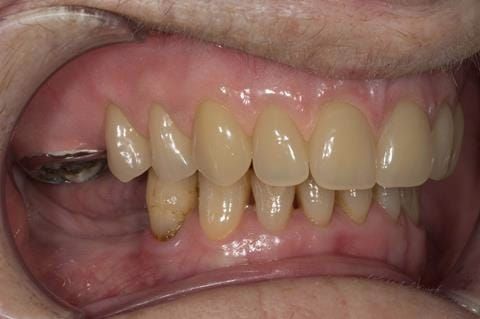

- UR7 - occlusal amalgam. 10- 20% alveolar bone loss. Healthy periodontium with reduced attachment level. No mobility.

- LL6 with large amalgam restoration - healthy periodontium.

- Cobalt chromium reinforced gasket denture - using a Molloplast B "O" ring to retain and stabilise the denture. This was my professional preference as this was the least invasive and simplest solution to this dental problem. Should the UR7 require removal in the future - an artificial tooth could be added - resulting in a complete denture. The patient would have adapted to the denture fully by this stage and have good neuromuscular control of the prosthesis.

Following consultation and second discussion appointment the patient chose to have option 2 namely, a window denture - maxillary cobalt chromium based partial denture. The clinical situation and treatment process is shown in detail below with photographs. The patient was successfully rehabilitated with this and her quality of life considerably improved. The clinical work was provided by Finlay and the technical work by Rowan.